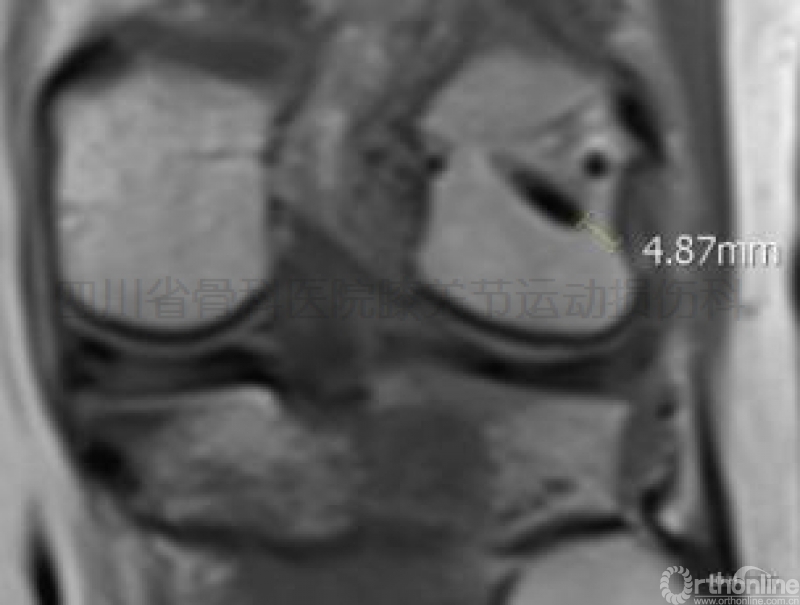

③导针尖端分别指向腘肌腱管区和股骨外髁之后下缘软骨区(图示七)。

图示七尸体试验显示RigidFix双鞘管经前内入口安全区逆向横穿后之剖面图。

a是在定位器引导下正常定位的鞘管;b是与a一样正常定位后,

术者故意将导针钻透股骨外髁骨皮质,其穿破区正好进入腘肌腱管。